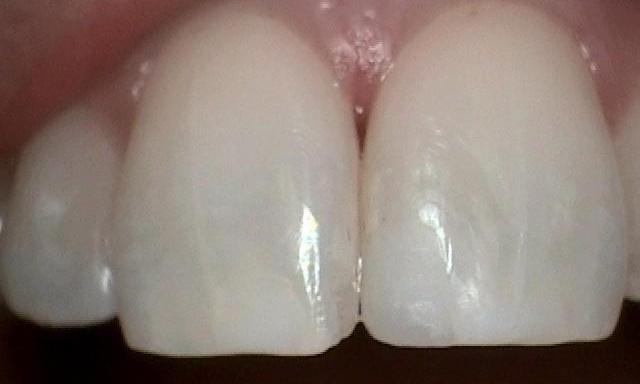

Although Fluoride is great at preventing cavities too much can stain your teeth. This patient was exposed to higher levels of fluoride when her teeth were developing as a child. These higher levels caused internal staining of her teeth. This staining cannot be corrected with whitening of the teeth because of the stain on the inside. Whitening can only correct staining on outside of teeth such as coffees, teas, or wines. The only way to correct internal staining is to cover the teeth with either crowns, veneers, or composite bonding. This patient elected to have veneers placed as they ...

This patient presented with moderate discoloration on their teeth due to high fluoride levels as a child. Fluoride is excellent at helping one not get cavities. However, too much fluoride consumed before the age of six years can result in stained teeth. There were two options to correct this staining: Veneers or tooth colored bonding. The patient chose tooth colored bonding and the procedure was completed in about an hour and a half.